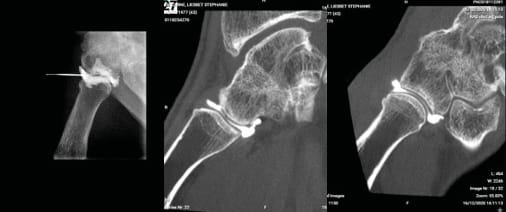

If there is any uncertainty, a CT scan will be carried out, preferably CBCT (3) as it offers greater detail and delivers lower radiation with contrast (Figure 14). This will allow an evaluation of cartilage quality. A trapeziometacarpal arthroscopy is better still (Figure 15).

Arthroscopy

An arthroscopy offers improved assessment of damage if conventional radiology is not conclusive. It replaces CT arthrogram and provides a better insight into the variability (Figure 15) of cartilage involvement at the trapezium and the articulating surface of the first metacarpal.